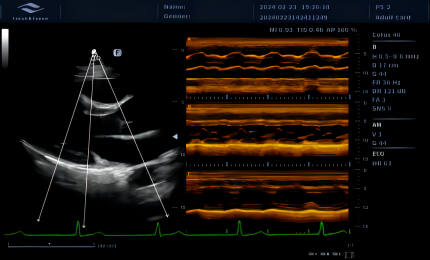

AM

Umożliwia ustawienie kursora M-trybu pod dowolnym kątem na cyfrowych obrazach dwuwymiarowych. Trzy linie próbkowania pozwalają lekarzowi mierzyć jednocześnie trzy pozycje, a każda linia próbkowania może być obrócona o 360°.